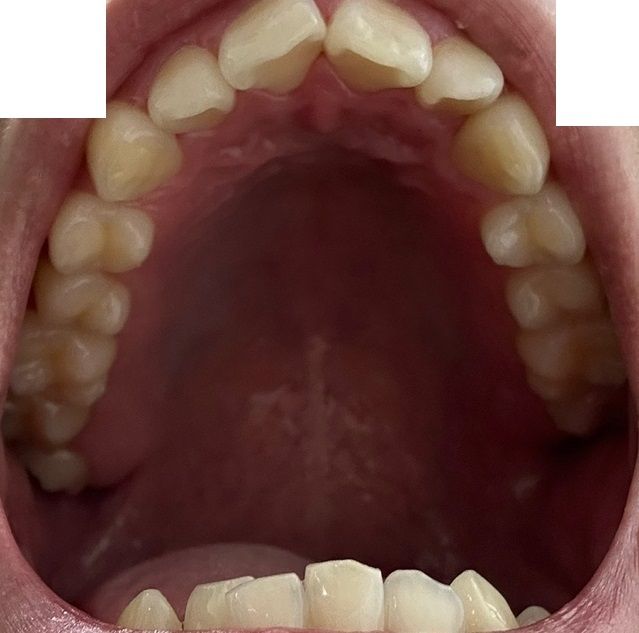

치아교정 해야될까요? 사랑니는 어떻게 해야할까요?

치아교정을 생각하게 된 계기는 지인의 권유인데, 교정을 받아도 괜찮을지 궁금합니다.

• 3번 째 사진

사진상으로 보면 치열등에 크게 문제가 잇어 보이진 않습니다. 교정은 환자분의 선택하시면될것같고, 사랑니 발치 여부도 교정진단을 먼저 받아보시는게 좋을것같습니다.